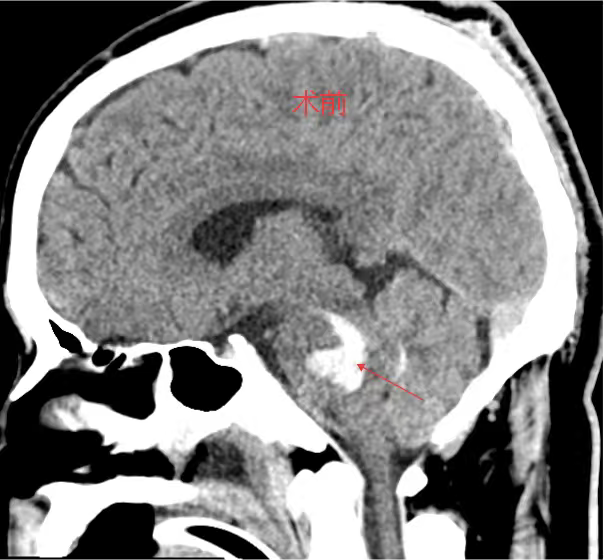

考虑到患者年轻、基础状况尚可,且出血部位深、传统开颅手术创伤大、风险高,医生团队决定采用脑立体定向仪引导下的微创穿刺血肿碎吸术。

主刀医生龙青山介绍,“我们利用立体定向系统,将穿刺误差控制在2毫米以内,仅需一个约3厘米的小切口,通过直径不足1厘米的骨孔置入穿刺管,直接进入血肿腔。”

手术过程历时一个多小时

共抽出近8毫升血块

术后复查显示

血肿清除率接近100%

术前